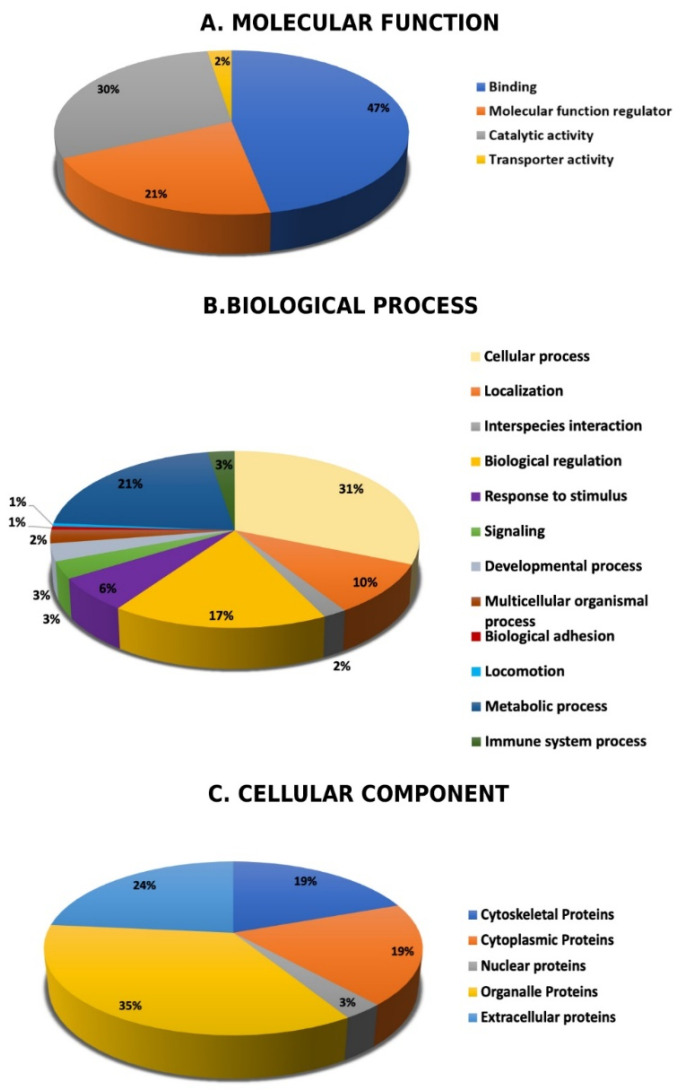

Following MS analysis, all 121 identified proteins between the CUD and control samples were subjected to the PANTHER classification system (http://www.pantherdb.org, accessed on 1 February 2021). The classification was performed according to their molecular function (Figure 6A), biological process (Figure 6B), and cellular component (Figure 6C). The main functional categories recognized were binding proteins (47%), catalytic activity (30%), and molecular function regulatory proteins (21%). Further, the identified proteins were located in the organelle region (35%), extracellular space (24%), followed by cytoplasmic and cytoskeletal regions, and each of these two account for (19%). The majority of the identified protein was involved in cellular process, metabolic process and biological regulations.